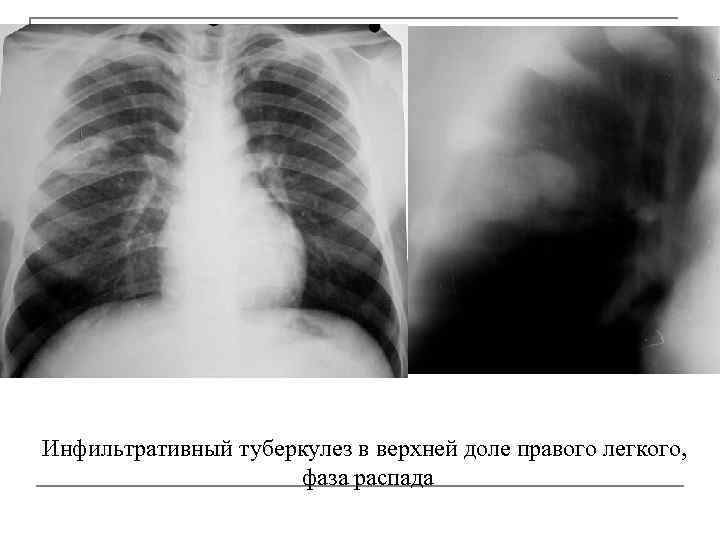

Симптомы и лечение инфильтративного туберкулеза легких

Раздел: Снимки-откровения